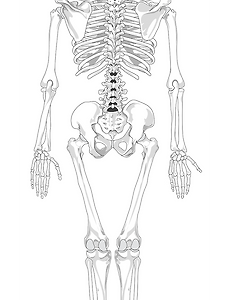

해부학적 자세와 근육의 부착점과 작용, 수축운동에 대해 글을 보기전에 유튜브의 영상을 본 후 다시보면 더 쉽게 이해하기 쉽고 공부하기 좋아 링크를 남겨드리겠습니다. 해부학적 자세 1. Axial body parts(축 몸통 부분): head(머리), neck(목), trunk(몸통) 2. Upper extremity body parts(상지 부분) :shoulder girdle(견갑대), arm(팔), forearm(아래팔), hand(손) 3. Lower extremity body parts(하지 부분) : pelvis(골반), thigh(허벅지), leg(다리), foot(발) 근육의 부착점과 작용 1. 이는곳(기시점이는곳(기시점: origin) 2. 닿는곳(정지점닿는 곳(정지점: insertion)..

해부학적 자세와 근육의 부착점과 작용, 수축운동에 대해 글을 보기전에 유튜브의 영상을 본 후 다시보면 더 쉽게 이해하기 쉽고 공부하기 좋아 링크를 남겨드리겠습니다. 해부학적 자세 1. Axial body parts(축 몸통 부분): head(머리), neck(목), trunk(몸통) 2. Upper extremity body parts(상지 부분) :shoulder girdle(견갑대), arm(팔), forearm(아래팔), hand(손) 3. Lower extremity body parts(하지 부분) : pelvis(골반), thigh(허벅지), leg(다리), foot(발) 근육의 부착점과 작용 1. 이는곳(기시점이는곳(기시점: origin) 2. 닿는곳(정지점닿는 곳(정지점: insertion)..